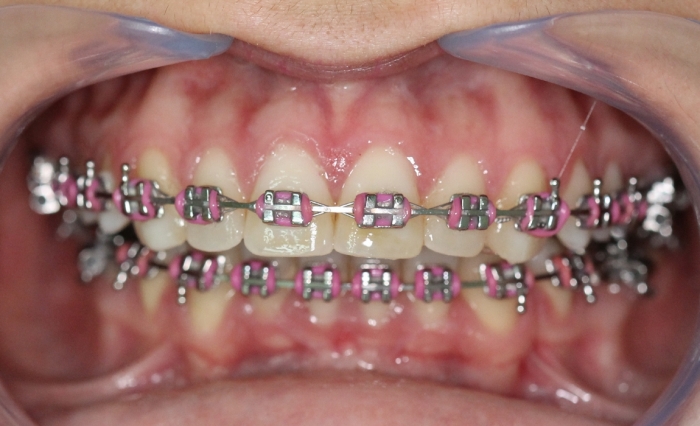

Mordida inicial

Mordida após a cirurgia